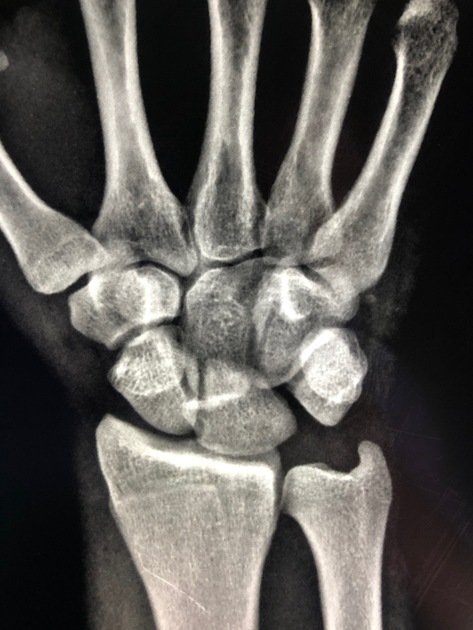

Stage III The disruption continues ulnarly — the lunotriquetral interosseous ligament (LTIL) ruptures; the triquetrum dislocates dorsally from the lunate; the entire distal carpal row (scaphoid + capitate + hamate + triquetrum) is now displaced dorsally relative to the lunate; the lunate remains in the lunate fossa Complete perilunate dislocation — the lunate is the only proximal carpal bone remaining in the lunate fossa; all others are displaced dorsally The classic perilunate dislocation radiograph; AP view: complete disruption of all three Gilula arcs; lateral view: the lunate is in the lunate fossa but the capitate, scaphoid, and triquetrum are all dorsal to it; the lunate still faces the radius but is beginning to tilt

• Gilula`s three carpal arcs (AP view): on a standard PA wrist radiograph in neutral position, three smooth continuous arcs should be identifiable; Arc I — the proximal convex surfaces of the scaphoid, lunate, and triquetrum (a smooth curve); Arc II — the distal concave surfaces of the scaphoid, lunate, and triquetrum (parallel to Arc I); Arc III — the proximal convex surfaces of the capitate and hamate; in a normal wrist, all three arcs are smooth, continuous, and parallel; ANY disruption, step-off, or discontinuity in these arcs indicates carpal instability or dislocation; in a perilunate dislocation, Arcs I, II, and III are all disrupted and the carpal bones overlap each other on the AP view creating a `crowded` appearance

• Key radiological signs summary: (1) AP view — loss of Gilula`s arcs; Terry Thomas sign (SL gap >3 mm); cortical ring sign (foreshortened scaphoid); triangular `pie-slice` lunate; overlapping carpal bones; (2) Lateral view — loss of the normal colinear radius-lunate-capitate alignment; DISI pattern (scapholunate angle >70°, capitolunate angle >30°); the capitate is dorsal to the lunate (perilunate) OR the lunate is volar to the capitate (lunate dislocation — `spilled teacup`); (3) AP + Lateral combined — the lateral view is the single most important view for diagnosis; most missed diagnoses are due to failure to examine the lateral view carefully

• Plain radiographs: AP, lateral, and oblique views of the wrist are the mandatory initial investigation; the lateral view is the most diagnostically important — examine carefully for the radius-lunate-capitate alignment; the AP view demonstrates Gilula`s arc disruption; the diagnosis is frequently missed because: (1) the AP view may appear confusingly `crowded` rather than obviously abnormal; (2) the lateral view is not examined carefully; (3) the treating clinician is not familiar with the normal carpal relationships; a systematic approach to every wrist X-ray (check Gilula`s arcs on AP; check R-L-C alignment on lateral) prevents missed diagnoses